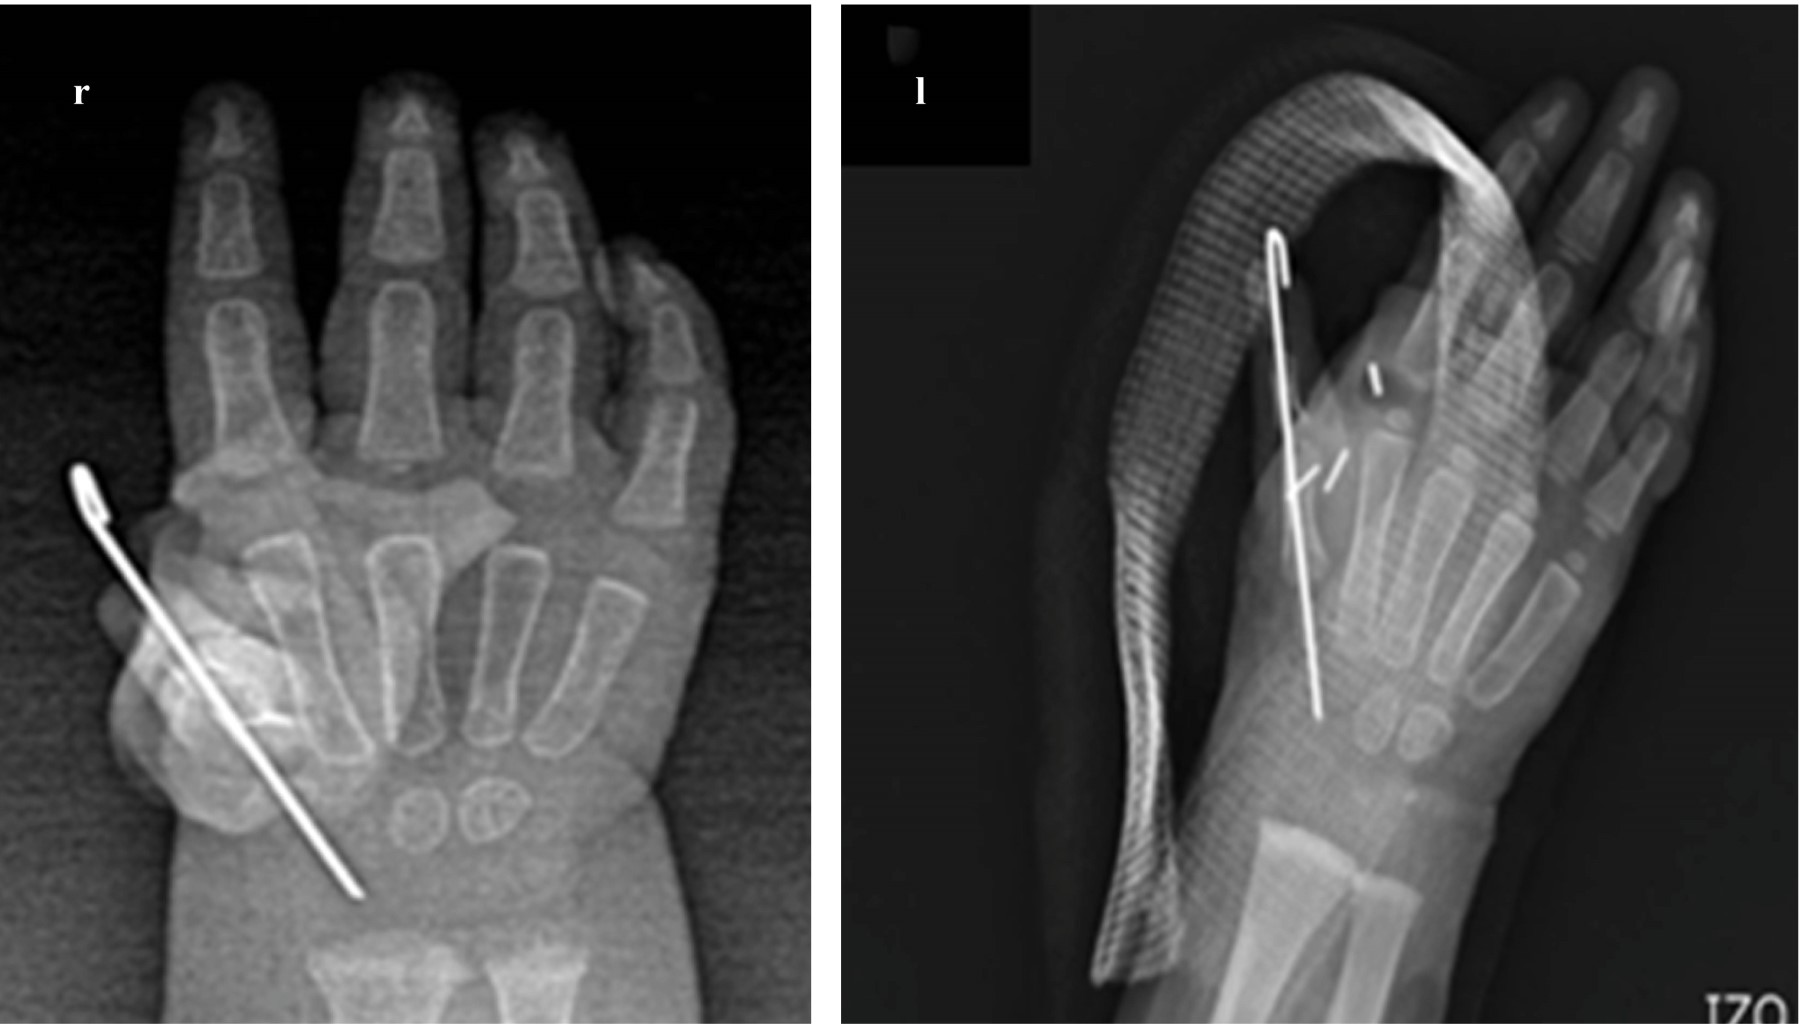

Subsequently, a section was made through the distal physis of the 1st radial metacarpal to perform a carpometacarpal arthrotomy and ablation of the first metacarpal and the second radial finger, maintaining the reduction in hyperextension of the metacarpal head and fixation with 0.35 K-wire, making the fixation of metacarpal to the distal carpus with 4-0 nylon suture.

The first radial ray was rotated longitudinally by 30°, palmar abducted by 40°, to avoid a hyperextension deformity and fixed with absorbable sutures and in position with a 0.35 K-wire. Based on previously described techniques (Pintilie et al10) tendon transfer was made from the common extensor of the fingers to the lumbrical with a interosseous tenodermodesis to the radial aspect of the finger, the interosseous fixation to remnants of pulleys with plication of the extensor apparatus extrinsic towards the thumb, so that the radial intrinsic muscles function as abductors, and the ulnar muscles as their synergists (Figure 3).

The closure of flaps was performed with 5-0 Nylon and, at the end of surgery, the thumb had a satisfactory aesthetic appearance, the attitude of the wrist in discrete flexion was still present, so we left a splint with a Spica, the only technical difference between surgeries was that a Hemoclip (vascular ligation) was used in the left hand (Figure 4). With ischemia on average of 97 min (99 min and 96 min respectively) and a total average surgical procedure duration of 193 min (197 min and 190 min respectively). We had no neurovascular complications.

Figure 4